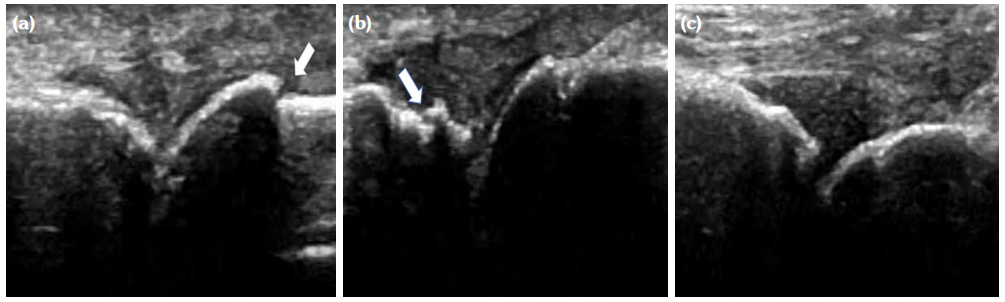

The degree of BE and synovial hyperplasia in SNRA or SPRA is more serious, and the blood flow signal is more abundant. However, the degree of synovial hyperplasia in osteoarthritis was mild, and no obvious blood flow signal was detected (Figures 1, 2, 3 and 4). Magnetic resonance imaging (MRI) studies of SPRA also showed serious BE (Figure 5).

Difference in ultrasound findings among SNRA, SPRA and non-RA groups

Among SNRA, SPRA and non-RA, there was no significant difference in the grades of SH, PD, BE, nor the number of cases of tendinitis and tenosynovitis between the SNRA group and the SPRA group (p>0.05) (Table 3). There were, however, statistically significant differences in the number of cases of SH1, SH3, PD and BE grades between the SNRA and non-RA groups (p<0.001). There was no significant difference in the number of cases of SH2, PD2, tendinitis or tenosynovitis between the SNRA and non-RA groups (p>0.05) (Table 4).